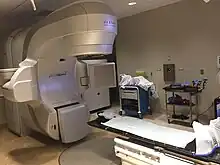

Radiation therapy of the pelvis, using a Varian Clinac iX linear accelerator. Lasers and a mould under the legs are used to determine exact position. | |

Radiation therapy or radiotherapy (RT, RTx, or XRT) is a treatment using ionizing radiation, generally provided as part of cancer therapy to either kill or control the growth of malignant cells. It is normally delivered by a linear particle accelerator. Radiation therapy may be curative in a number of types of cancer if they are localized to one area of the body, and have not spread to other parts. It may also be used as part of adjuvant therapy, to prevent tumor recurrence after surgery to remove a primary malignant tumor (for example, early stages of breast cancer). Radiation therapy is synergistic with chemotherapy, and has been used before, during, and after chemotherapy in susceptible cancers. The subspecialty of oncology concerned with radiotherapy is called radiation oncology. A physician who practices in this subspecialty is a radiation oncologist.

Medical linear particle accelerators, developed since the 1940s, began replacing X-ray and cobalt units in the 1980s and these older therapies are now declining. The first medical linear accelerator was used at the Hammersmith Hospital in London in 1953.[72] Linear accelerators can produce higher energies, have more collimated beams, and do not produce radioactive waste with its attendant disposal problems like radioisotope therapies.